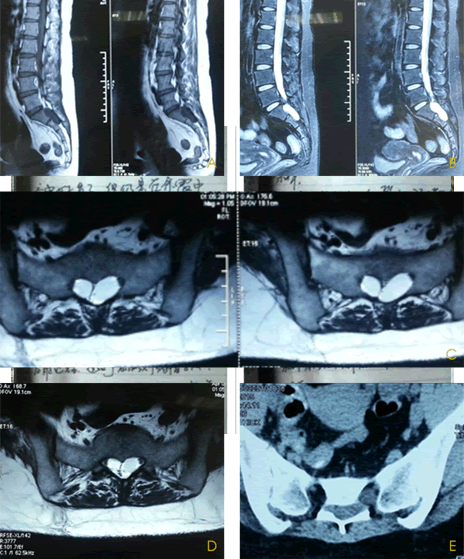

1、复杂症状的骶管囊肿

女,35岁,间断发作性下腹会阴双下肢疼痛8年,近两月加重,床上翻身,迈步走道剧烈疼痛。不能睡觉,不能站立,只能窝在轮椅里,靠止痛药度日。查体除右侧鞍区针刺痛觉敏感,余无特殊,病例详情请至云医#病例讨论#版块查看。

2、骶管病变

男,55岁,左侧腰臀部疼痛5年,渐加重,伴会阴部坠胀不适,久坐久站明显,病例详情请至云医#病例讨论#版块查看。